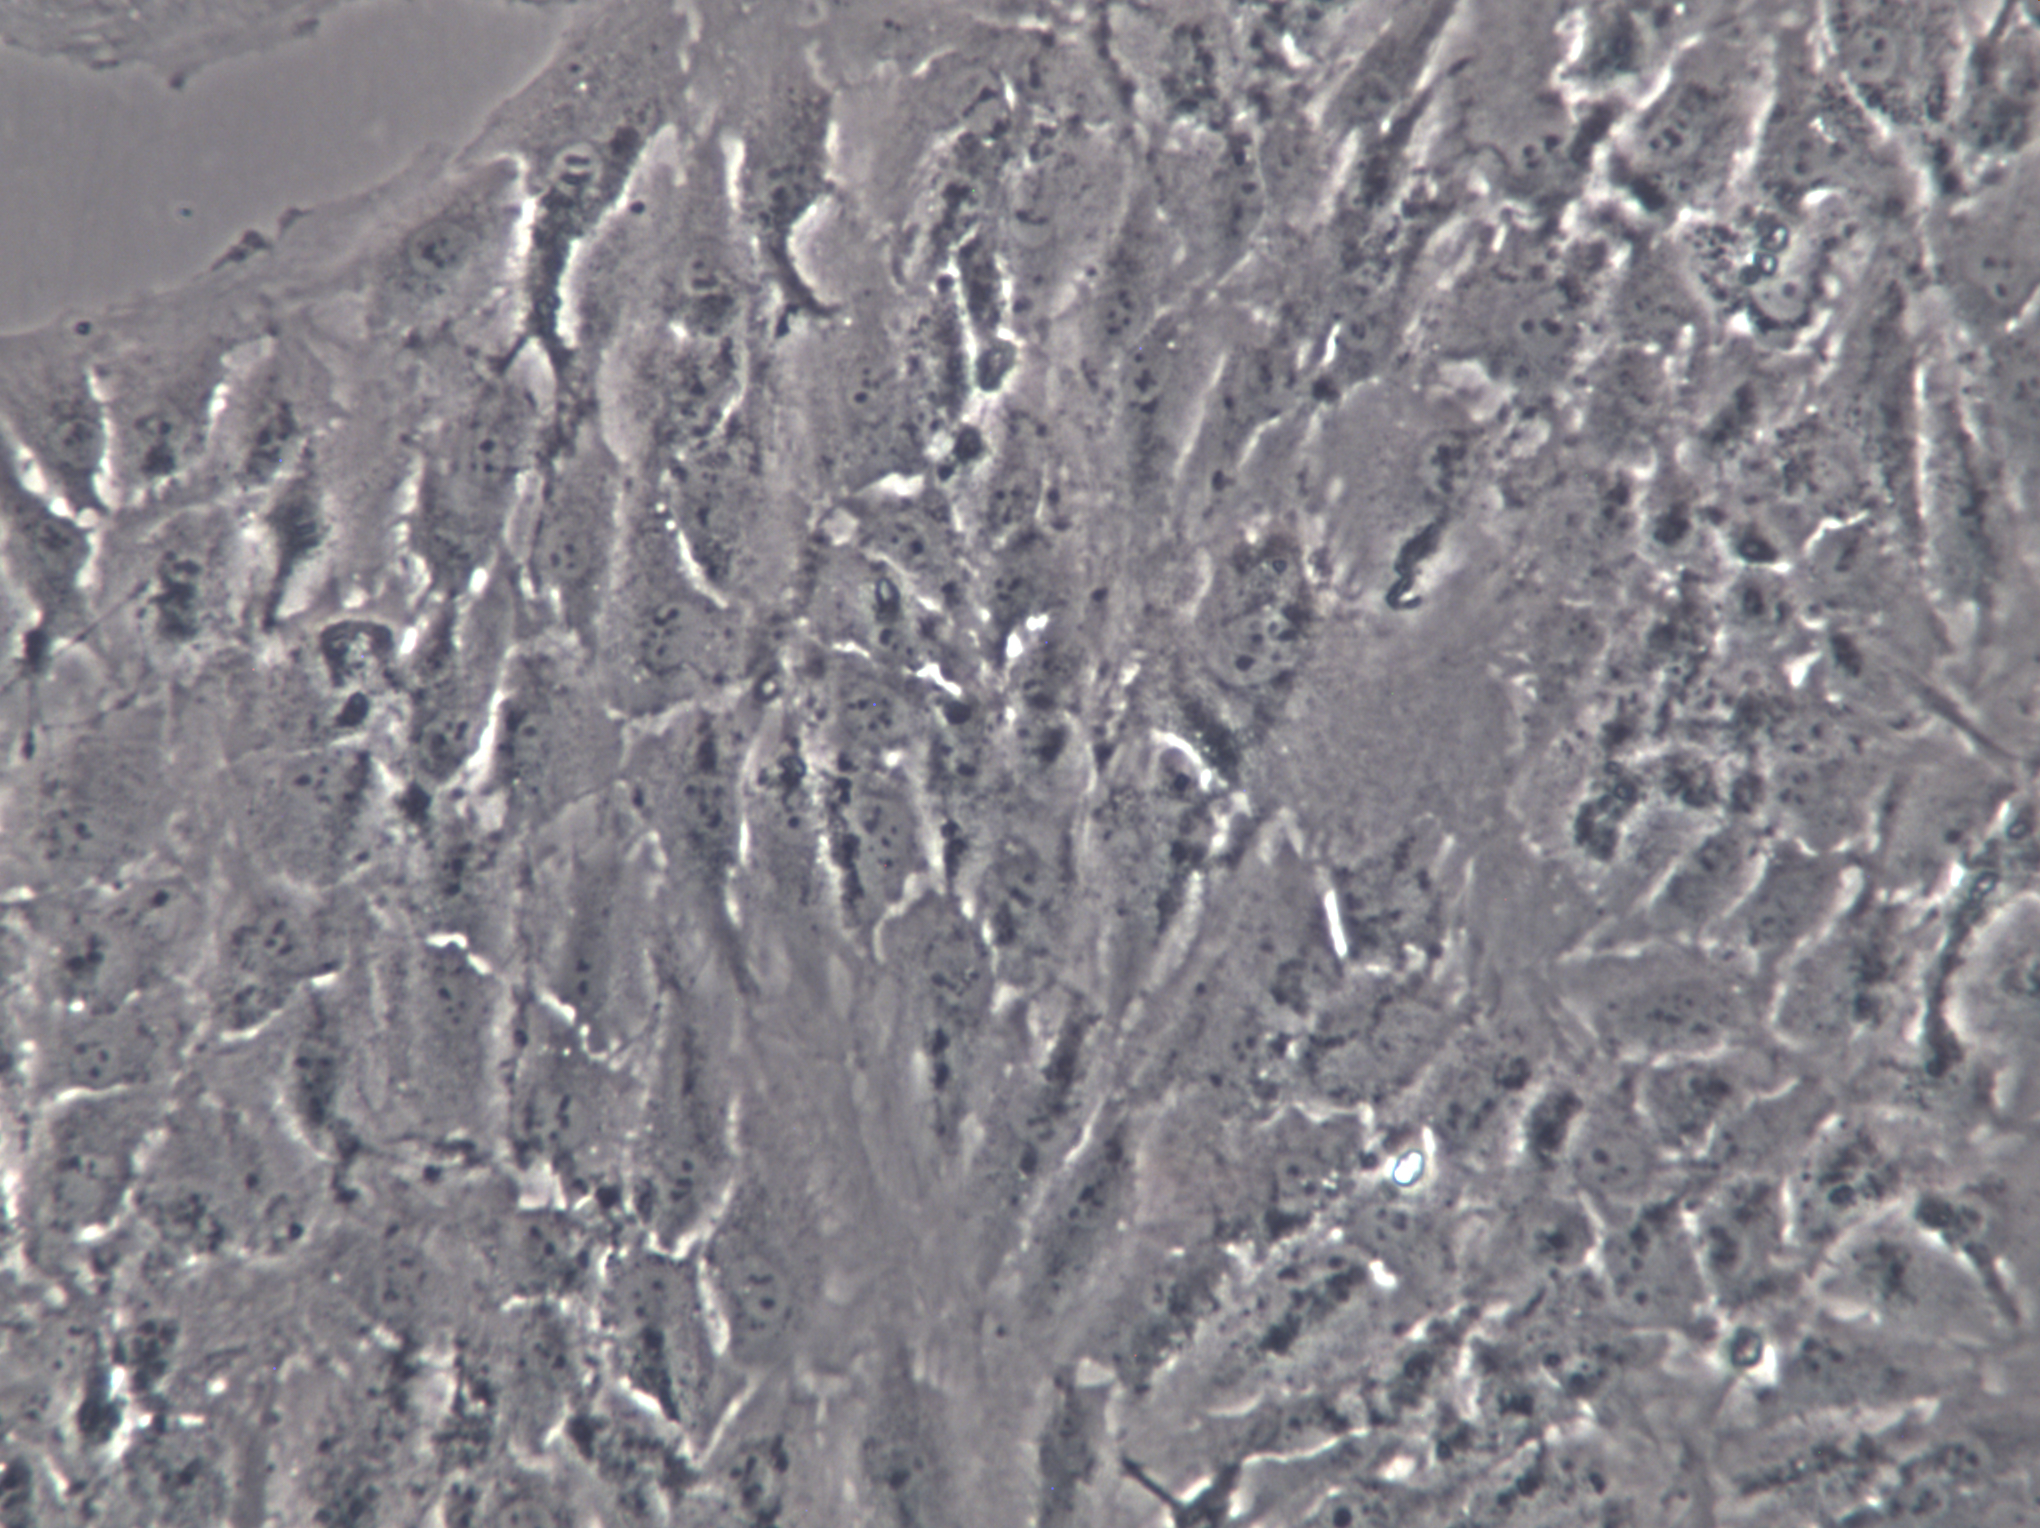

1、細胞名稱:人卵巢顆粒細胞;KGN

4、背景資料:該細胞株是顆粒細胞瘤。細胞在加入人體絨膜促性腺激素后可能產生孕酮。細胞生長緩慢。

4、圖片: